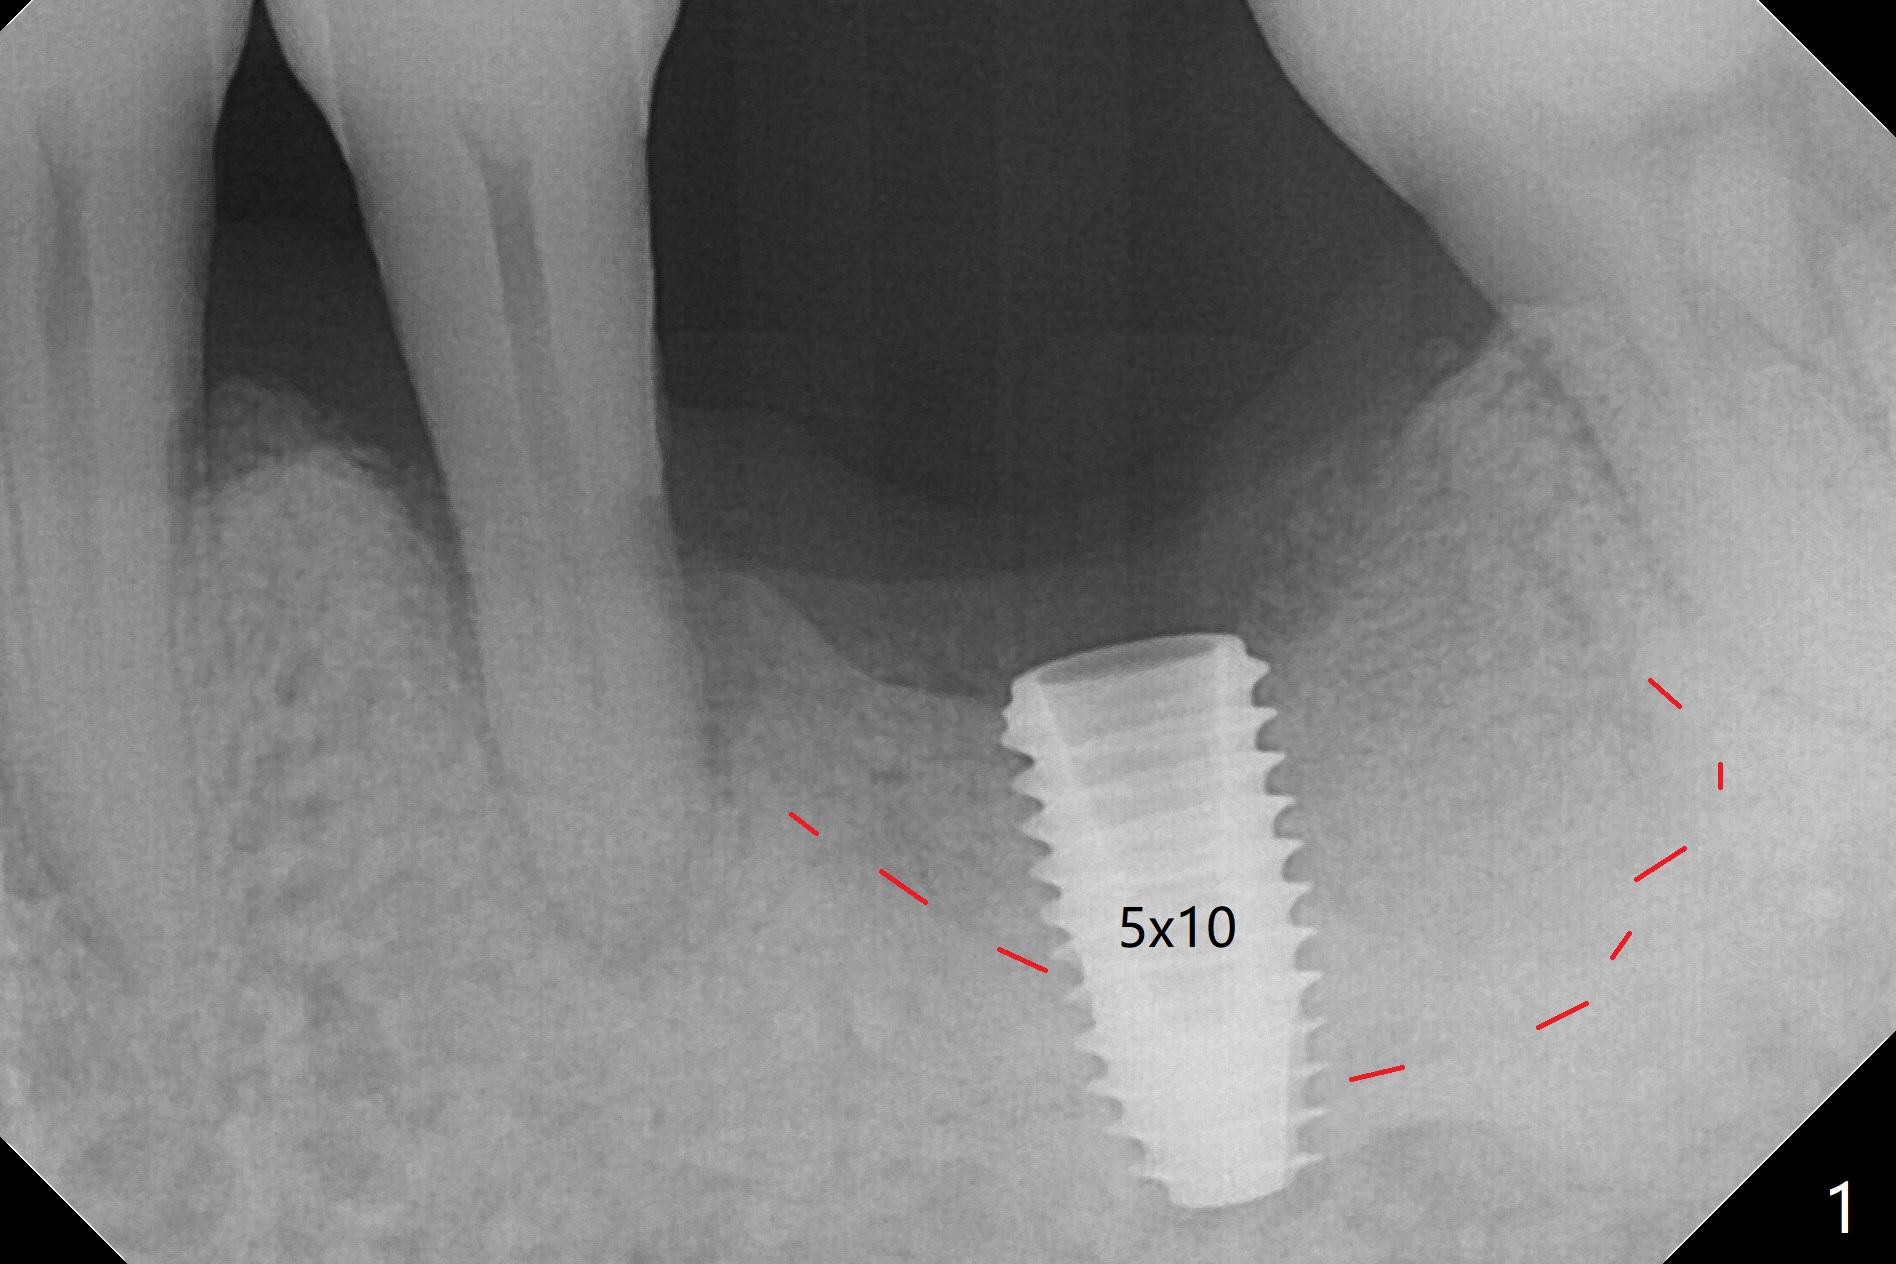

Osteotomy shows two layers of bone. The first one feels slightly less dense than the normal bone (Fig.1 above the red dashed line), while the second one is extremely hard (3-4 mm in depth). For the last 1.5 mm of the osteotomy, the 4.5 mm drill has to be withdrawn for bone shaving removal before finishing the osteotomy. In all the graft bone contributes to implant stability (insertion torque > 50 Ncm). At least the implant is surrounded by the bone with less likelihood of developing periimplantitis. As usual, there is clearance from the Inferior Alveolar Canal (Fig.2 yellow dashed line). After quick surgery, the patient wonders why he does not get a provisional. The advantage of the latter may reduce the chance of shifting of the neighboring teeth (with increased pdl, Fig.2). In fact he requests final restoration in a month. Some of my patients travel a lot. Miao afraid of dentistry. But after #30 implant placement with guide, she is fearless. A permanent crown was delivered in 2 months. Two or 3 months later she returned for #14 guide. Mr. Zheng has the similar situation. He will stay in his home country for 2 months. I want to satisfy him although I have not promised to. Do you have any suggestions?